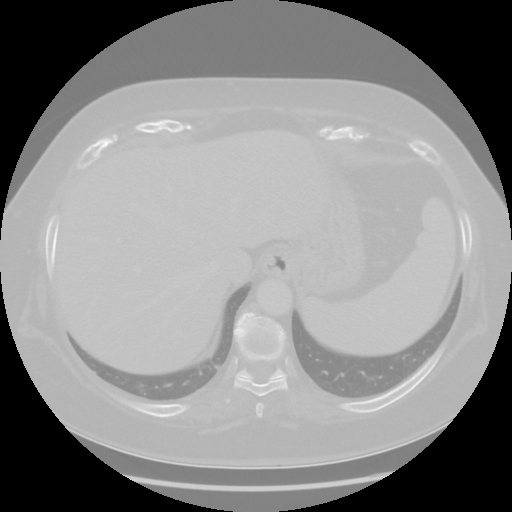

Original NATIVE CT scan (input)

No window - Raw intensity values

Lung window (WL -600, WW 1500 β†’ Low βˆ’1350, High +150)

Mediastinum window (WL 40, WW 400 β†’ Low βˆ’160, High +240)